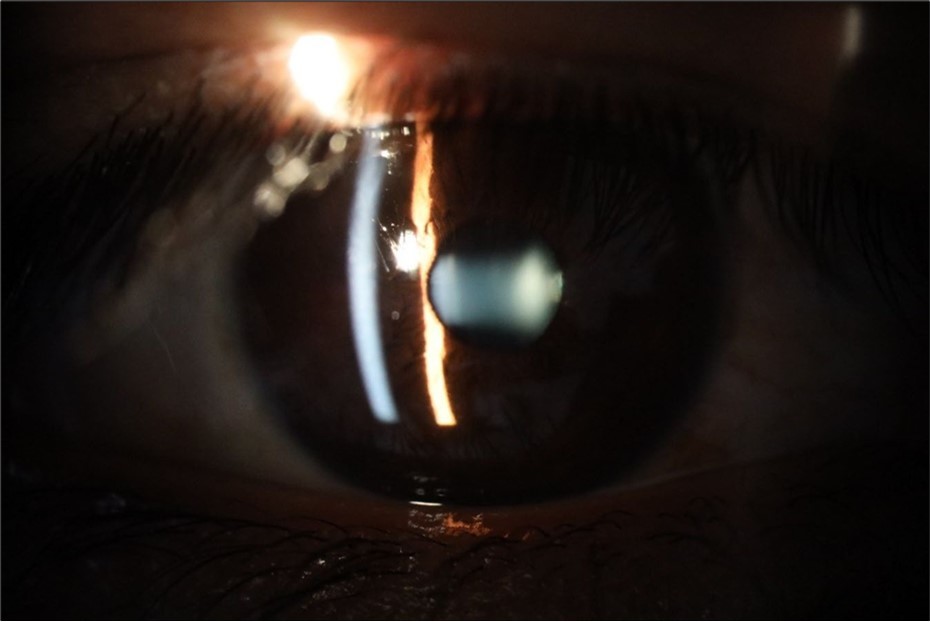

Figure 6.Slit-lamp examination showed a solution of continuity in the left temporal region, which fortunately only affected the conjunctiva and Tenon's capsule, while the sclera was unscathed.

Figure 16.The anterior segment of the right eye shows the vitreous with greater transparency. The cornea and lens, as well as the anterior chamber, are in good condition.

Figure 21.The anterior segment of the right eye responds with difficulty to mydriatics, which is usual in diseased eyes.

Figure 26.The macrograph of the anterior segment of the right eye (affected) shows very good transparency of the cornea, anterior chamber, lens, and vitreous.

Figure 31.The photograph of the right eye shows an almost normal mirror reflection, as well as a better pupillary dilation.

Figure 32.The macro photograph of the right eye shows us a cornea, anterior camera, and crystalline lens in very good condition.